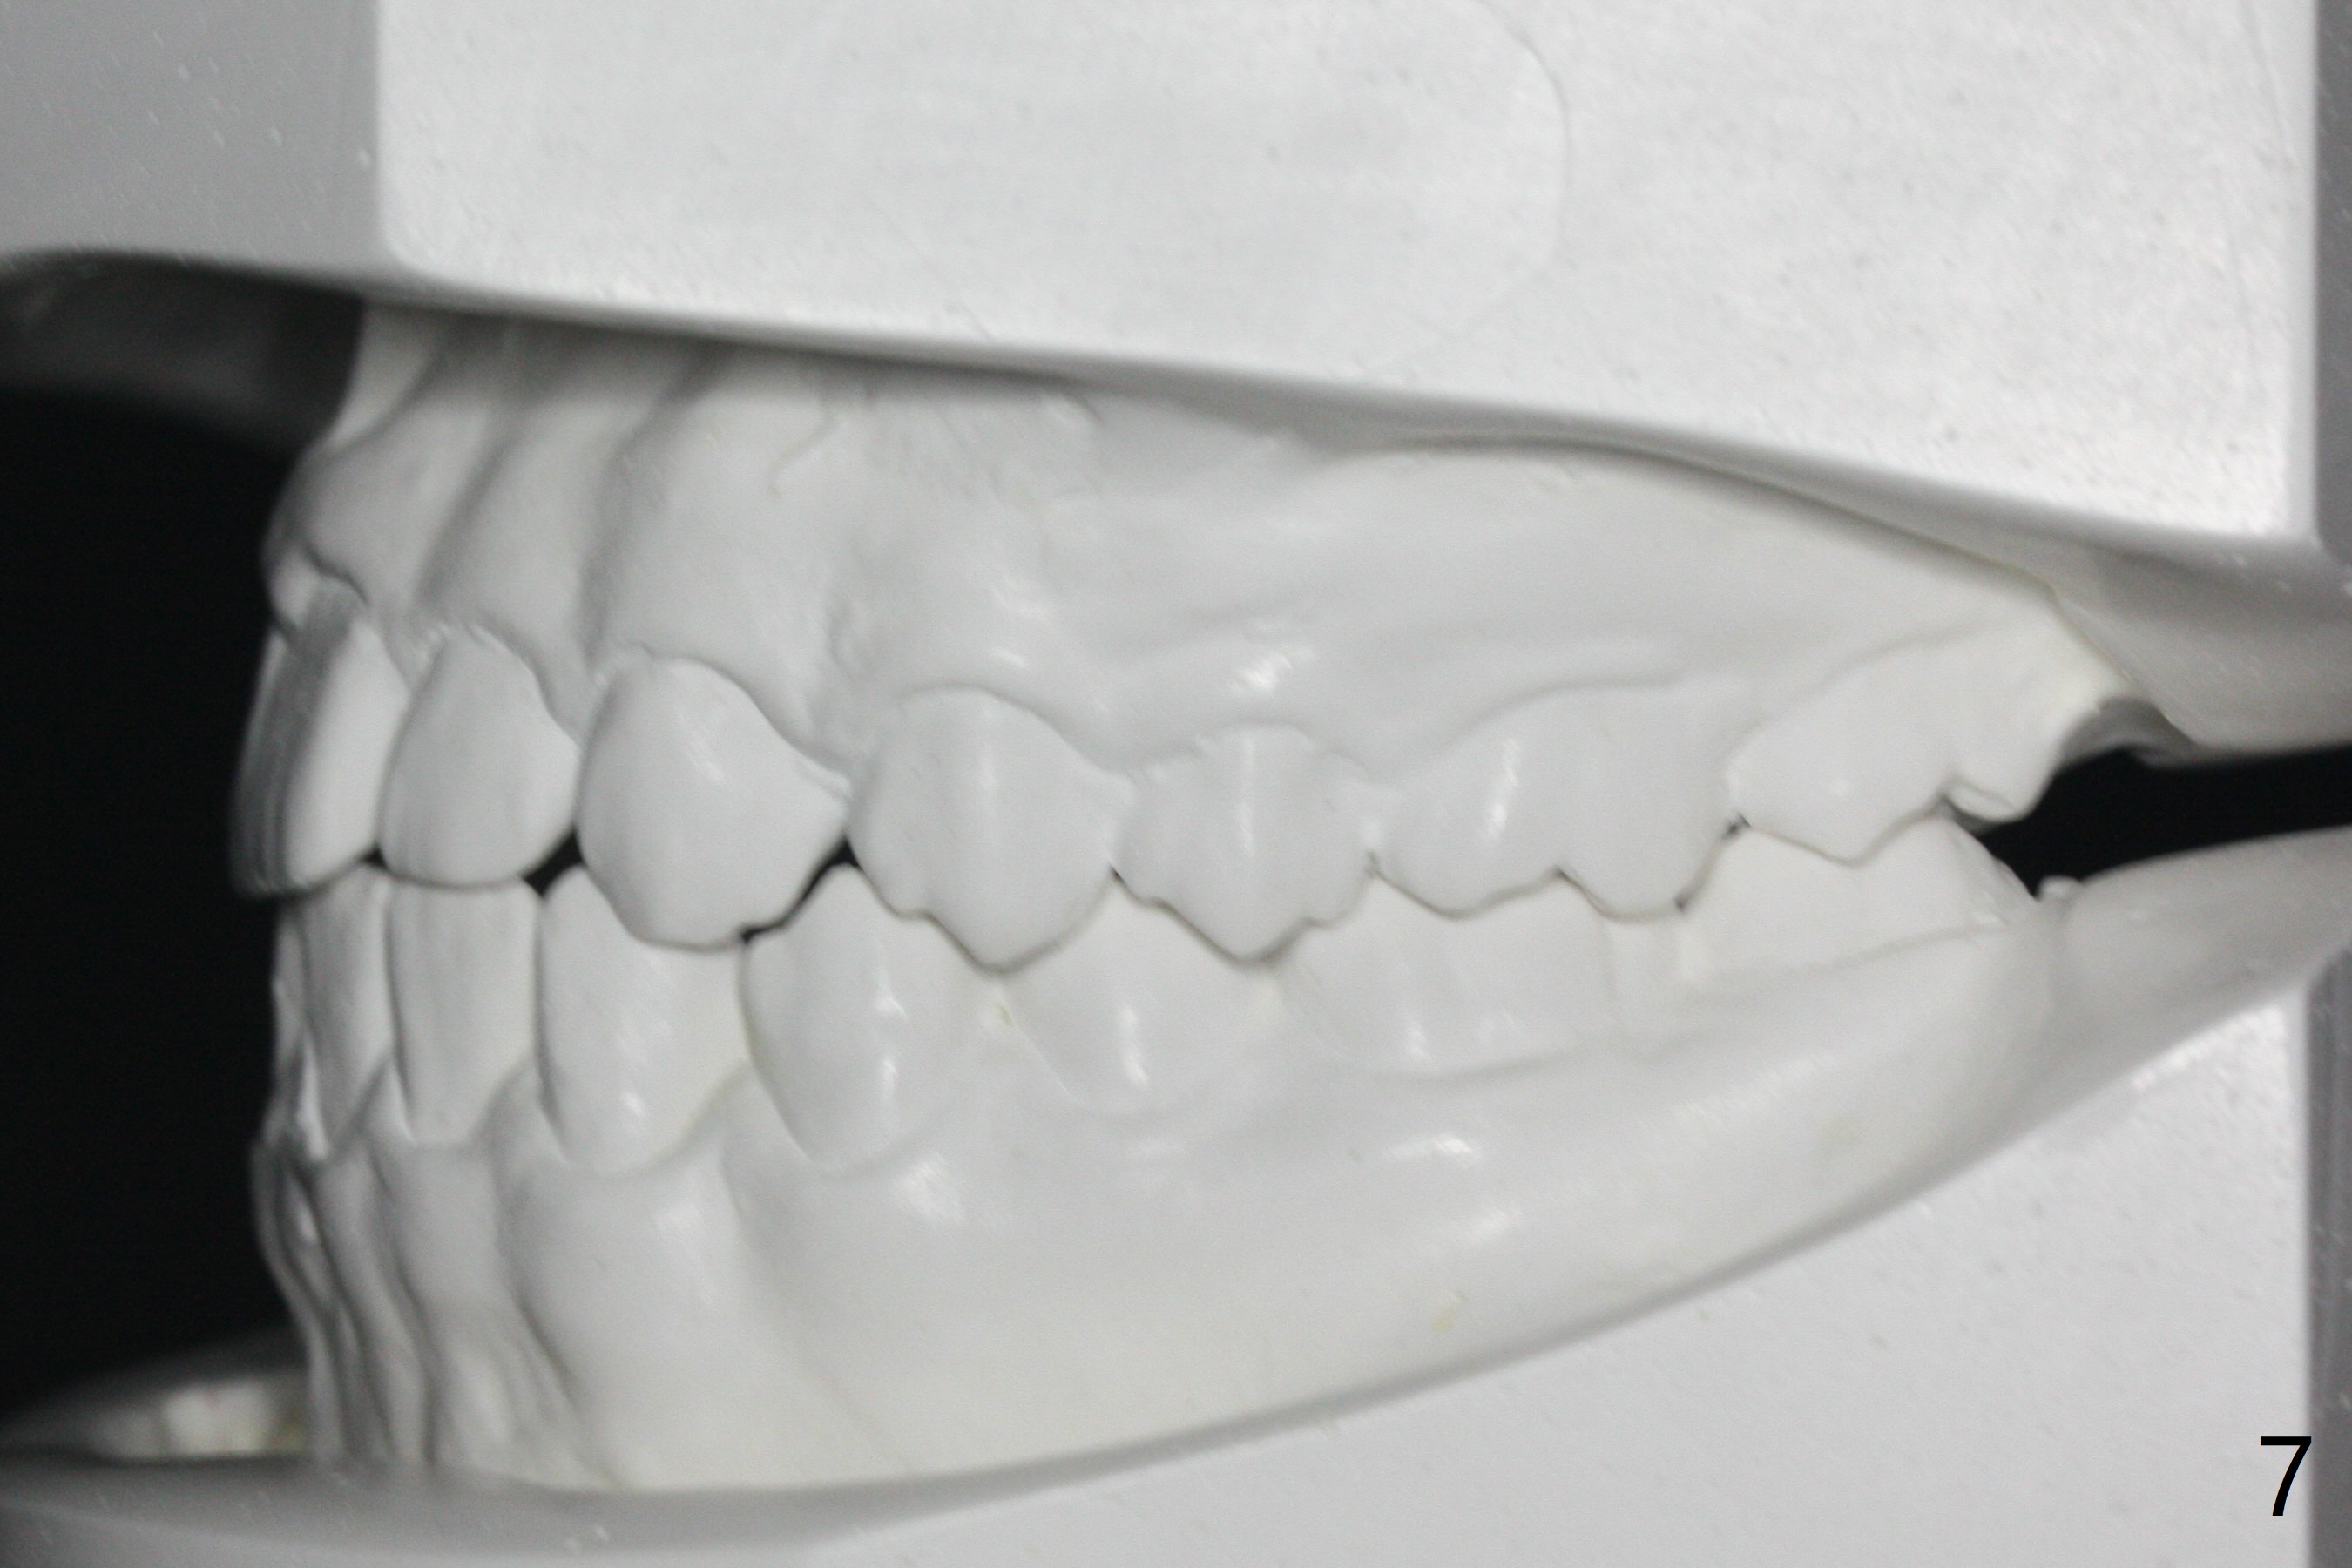

A 14-year-old man requests ortho because of crowding lower anterior and UR missing lateral (Fig.1-4). Open space for the future implant at UR2 will correct upper midline deviation (Fig.1) and change Class II malocclusion to I on the right (Fig.6, as compared to Fig.7). To control UR1,3 root torque, bracketing on these 2 teeth will be intentionally off (Fig.5). The treatment will take ~ 2 years. Prior to implantation at UR2, what type of prosthesis should be made?